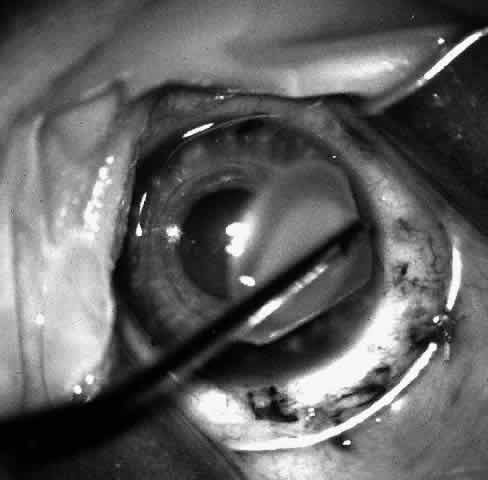

Sixteen to 22 interrupted 10-0 nylon sutures are placed to secure the edge of the lens in the peripheral corneal stroma trough. The first eight sutures are placed with the edge of the lens lying over the circular trephine mark (Fig. 10). As with any corneal transplant surgery, the second suture is the most important in centering the lens. All knots must be tied in such a way that the knots may be buried easily. At the same time, the sutures must not be tightened so tightly that compression occurs with the lens. My personal preference is for a 2-1-1 surgeon's knot. Care should be taken to prevent the lens from being sewn eccentrically into the bed, to prevent astigmatism. After the first eight sutures are placed, the edge of the lens is tucked into the stromal bed all around (Fig. 11) and the remaining 8 to 14 sutures are placed to fasten the lens securely in place (Fig. 12). The sutures are rotated so that the knots are buried in the recipient cornea. This allows the surgeon to remove the sutures at a subsequent examination under anesthesia (EUA) by means of traction directed peripherally without dehiscence of the wound.

Fig. 10. Lenticule is sutured with interrupted 10-0 nylon sutures.

Fig. 11. After the first eight sutures are in place, the edges of the lenticule are tucked into the bed.

Fig. 12. The remaining eight sutures are placed with the lenticule edges tucked.